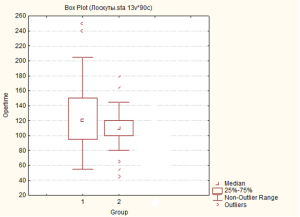

Мал. 6. Тривалість оперативного втручання в досліджуваних групах: група 1 – група зі стандартним передопераційним обстеженням; група 2 – група із модифікованим передопераційним обстеженням (праворуч).

Таким чином, застосування розширеної програми передопераційного обстеження із застосуванням контрастної КТ-ангіографії не призводить до скорочення тривалості оперативного втручання. Проте, більш репрезентативним в аспекті клінічної результативності є не тривалість оперативного втручання загалом, а, безпосередньо, тривалість етапу препарування клаптя, скорочення якої є доведеним при застосуванні контрастної КТ-ангіографії для передопераційного планування клаптя на судинній живлячій ніжці, що містить єдину перфорантну артерію.